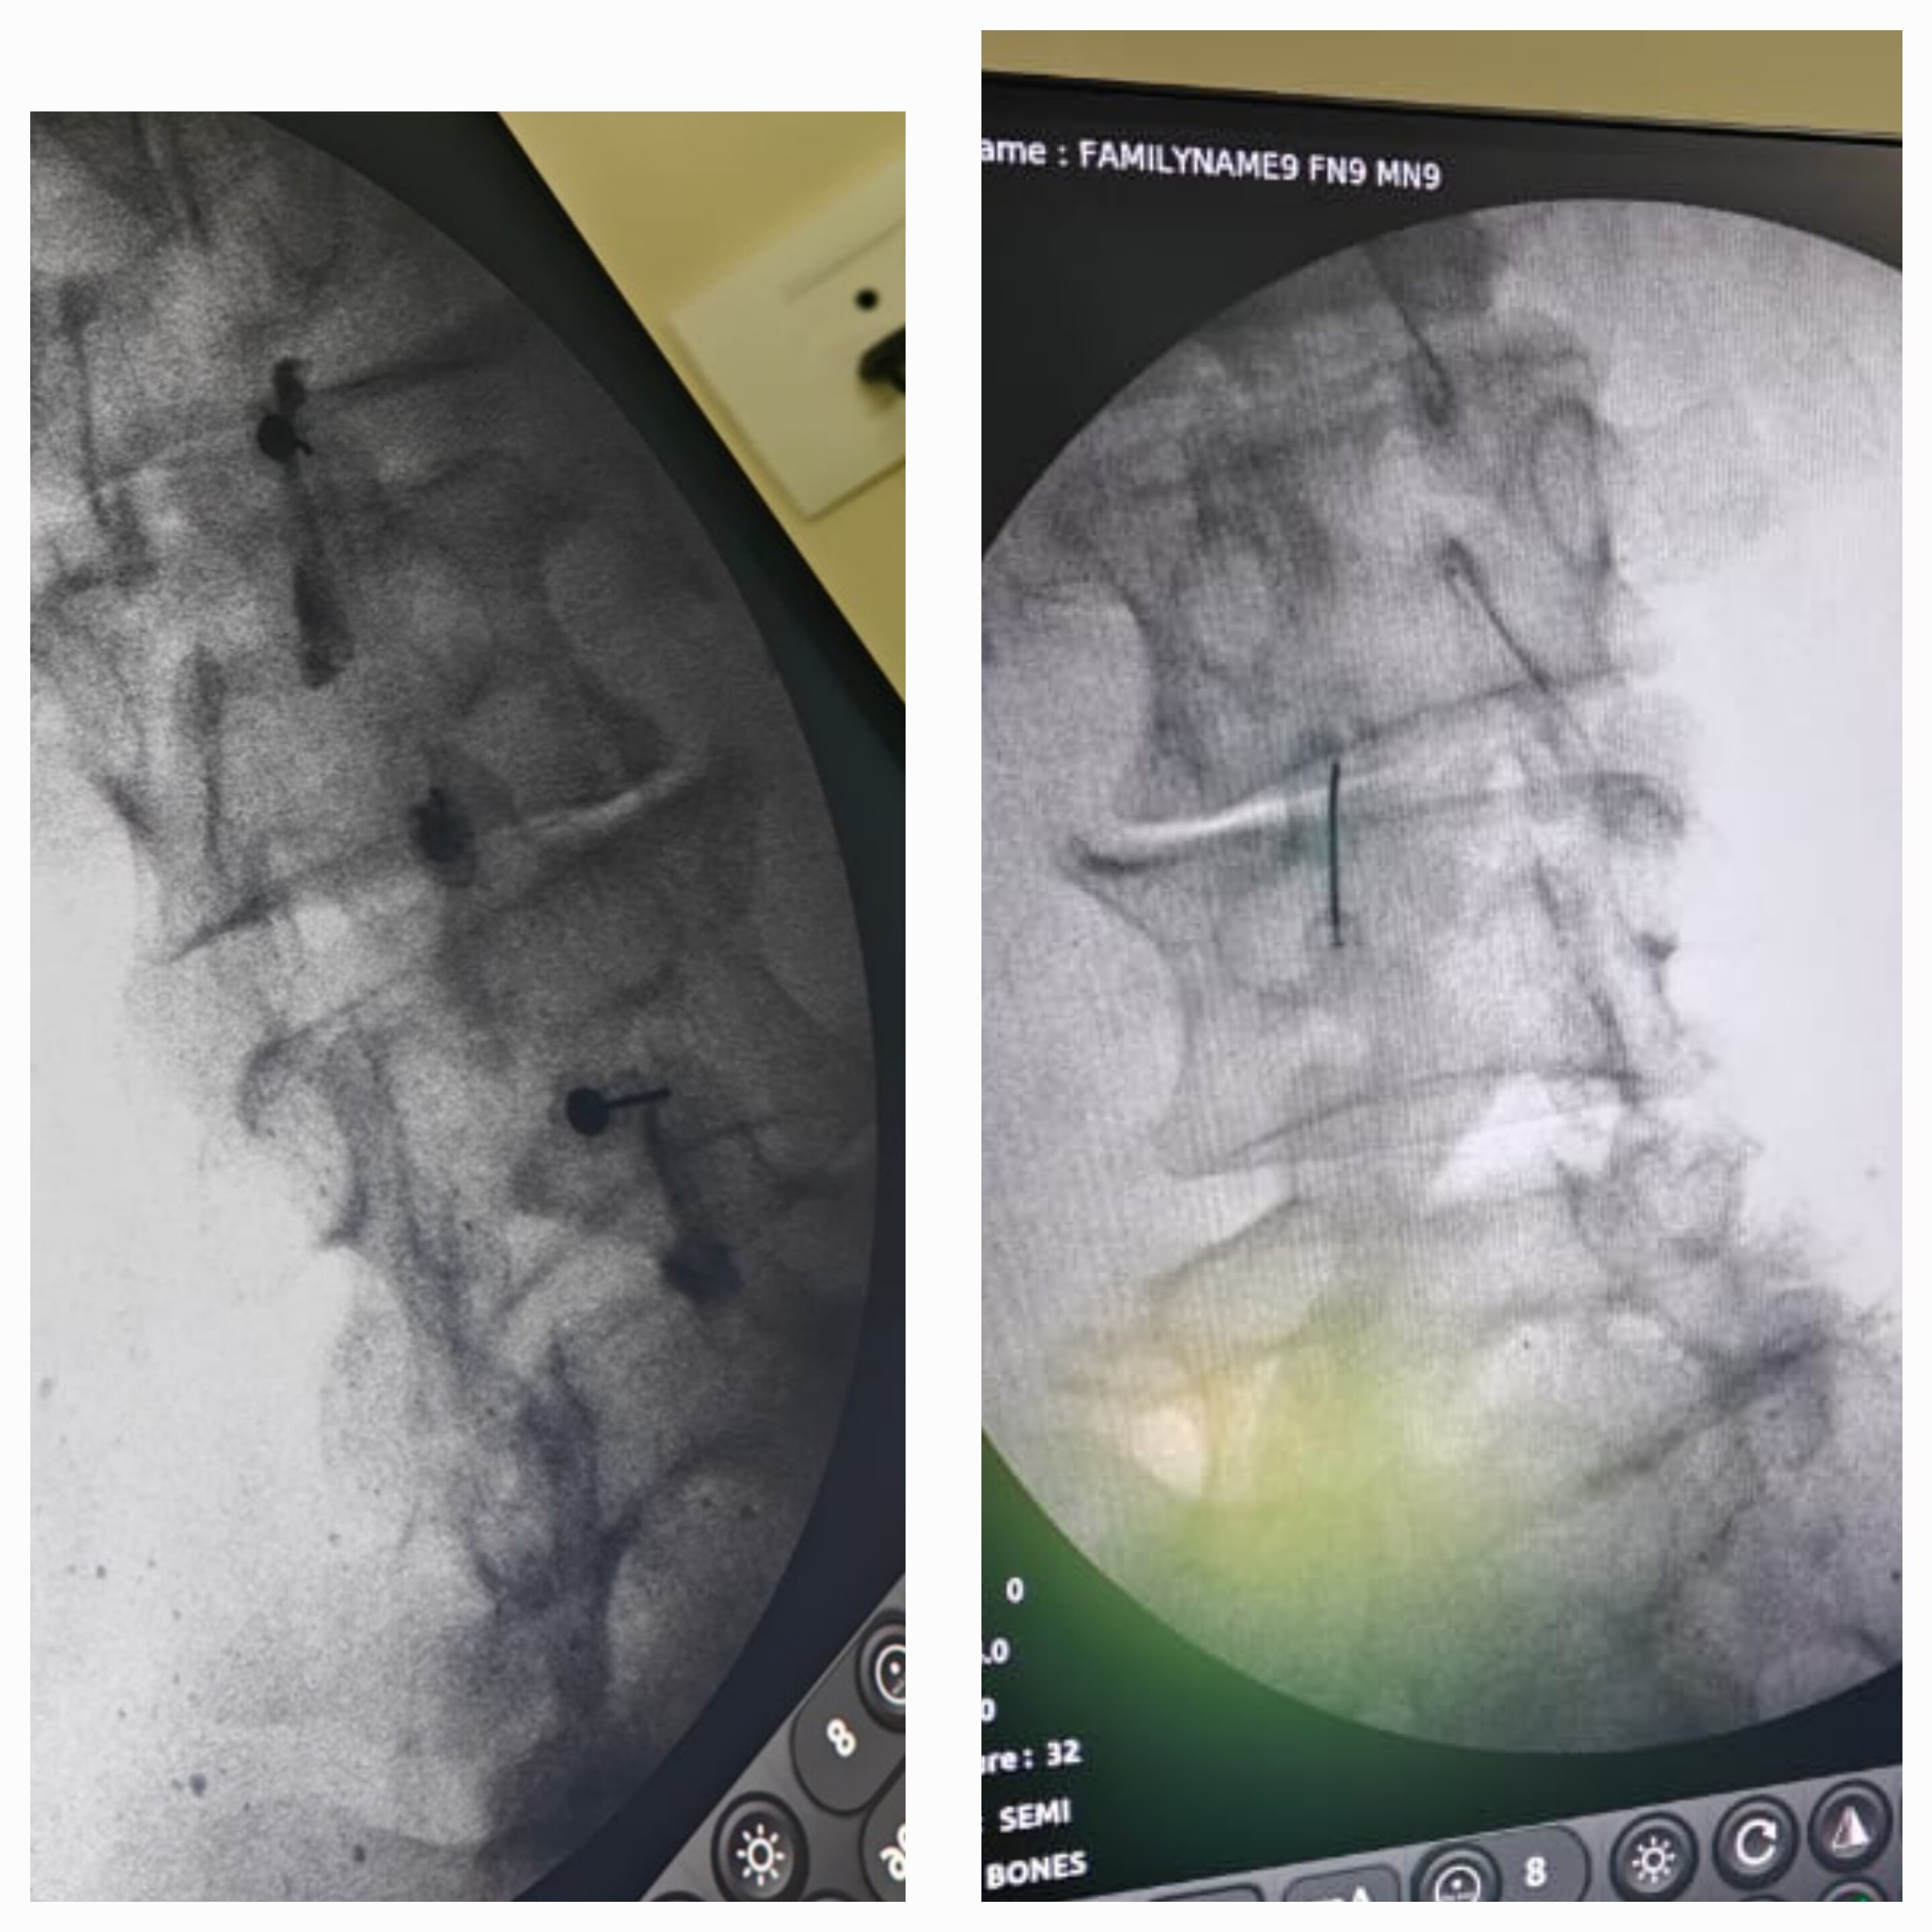

Sunshine Ortho Pain Superspeciality Hospital is the Best Multispeciality Hospital, Orthopedic Hospital in Wakad, Hnjewadi, PCMC and Pune. We are specialized in Orthopedic Surgeries, Robotic Joint Replacement Surgery, Hip and Knee Replacement Surgery, Complex Trauma And Pelvi Acetabular Surgery, Spine Surgery, Sports Medicine And Arthroscopy, Regenerative Therapy/Prolotherapy, Shoulder Surgery, Knee Surgeries, Foot And Ankle Treatment in Wakad, Hinjewadi, PCMC and Pune.